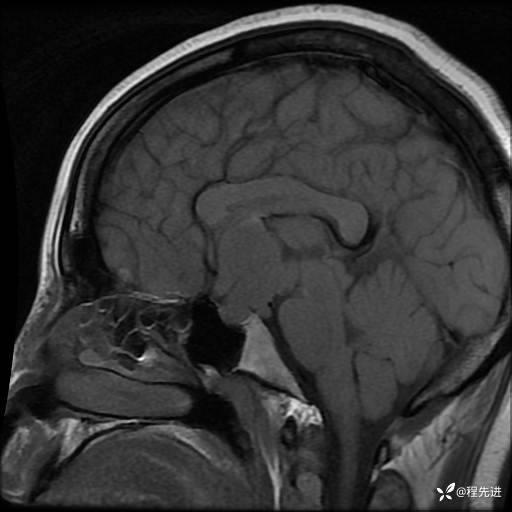

T1+C: